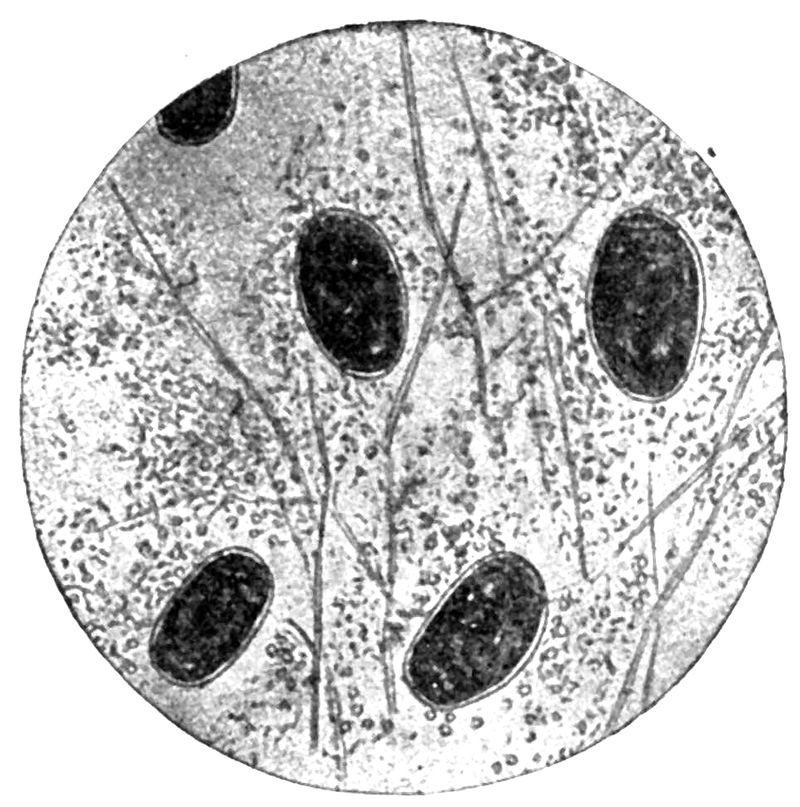

Fig. 3.Plasmodium vivax.(Benign tertian) Development of schizonts of nonsexual cycle in peripheral blood of man. Red cell swollen and stains feebly. Note Schüffner’s dots. X 2200. (MacNeal after Doflein.)

Fig. 5.Plasmodium vivax. Mature schizont and merocyte. Found in the blood just before and at onset of chill. X 2200. (MacNeal after Doflein.)

Fig. 6.Plasmodium malariae. (Quartan.) Development of nonsexual parasite in blood of man. X 2200. (From MacNeal after Doflein.)